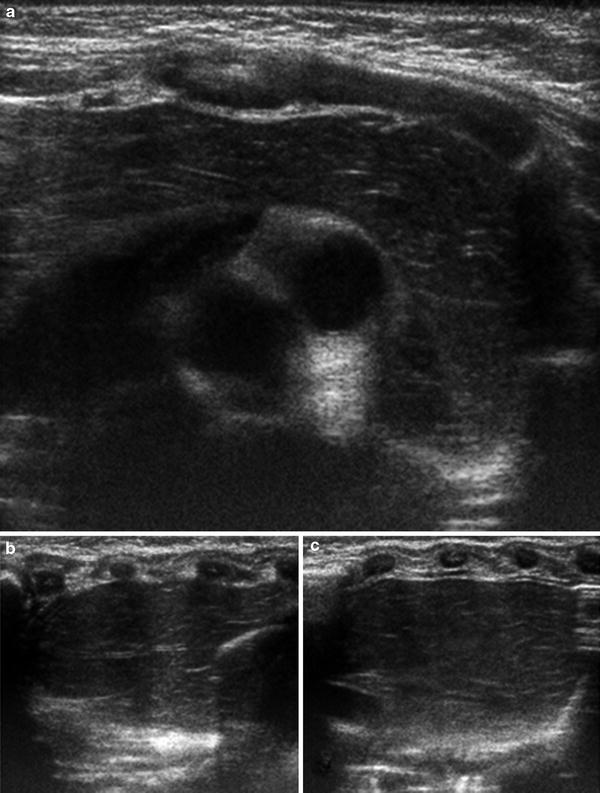

Ultrasonographic view of the fetal thymus at 27 weeks of gestation Thymus X Ray Baby In infants and young children, the thymus can be impressively large on frontal radiographs. The embryology and anatomy of the thymus, its normal variations and ectopic locations, dynamic changes in the thymus, and various thymic disorders are discussed, with emphasis on differentiating benign and malignant processes to avoid unnecessary invasive procedures. The classic “sail” sign, a sharply demarcated. The aim. Thymus X Ray Baby.